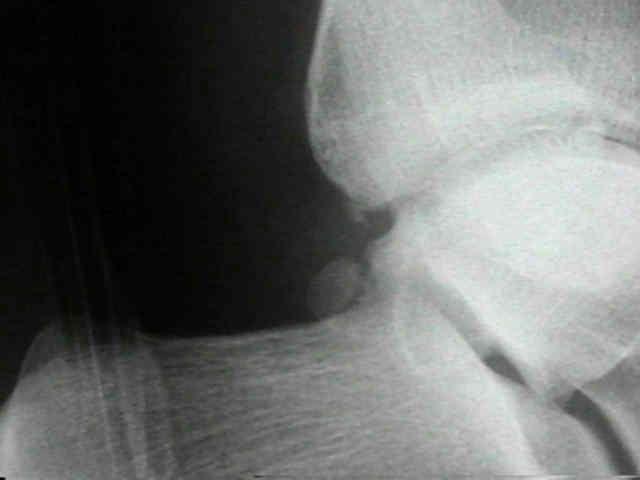

Fracture of the os trigonum - 발목 후면부 유리체

The os trigonum is an inconsistently present accessory bone of the foot situated at the posterolateral aspect of the talus. It may be radiographically confused with fractures of the posterior process of the talus. Fracture of the os trigonum per se is extremely rare. Hyperplantarflexion of the ankle is the mechanism of injury in which the os trigonum is compressed between the posterior malleolus of the tibia and the tuber calcaneus. Computed tomography is the choice of imaging modality in cases where fractures of posterior talus structures, including the os trigonum, are suspected. A high index of suspicion is necessary to diagnose a fracture of the os trigonum after a severe plantarflexion injury to the ankle. Conservative treatment is usually successful. We report a case of a fracture of the os trigonum, its clinical features,  treatment and significance.